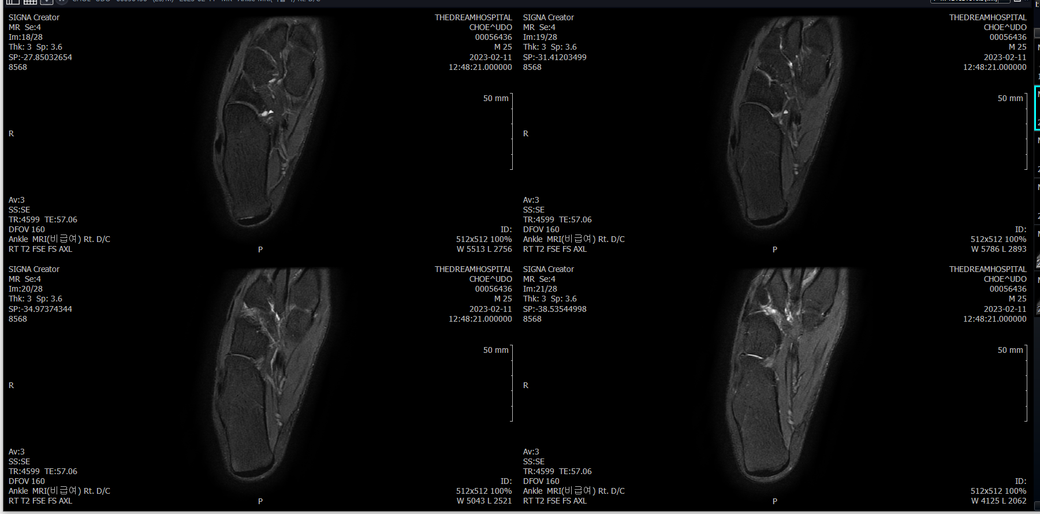

오른발목 mri 전체사진입니다. 제가 병원을 갈수없는상황인지라.... 봐주시면 감사하겠습니다.

엑스레이에서는 문제가 없다고 하여 오른발목 mri촬영했습니다.

우선 전반적으로 봤을 때 큰 이상은 없어보입니다.

전거비인대 등도 저명한 손상은 없는 것 같아 보이지만, 어느 부분의 통증 등으로 인해 촬영을 하셨는지 말씀을 해주신다면 보다 정확한 병변파악이 가능하겠으며, 병원에서 판독이 완료되신다면 전화 등으로 문의를 해보시는 것이 좋겠습니다.